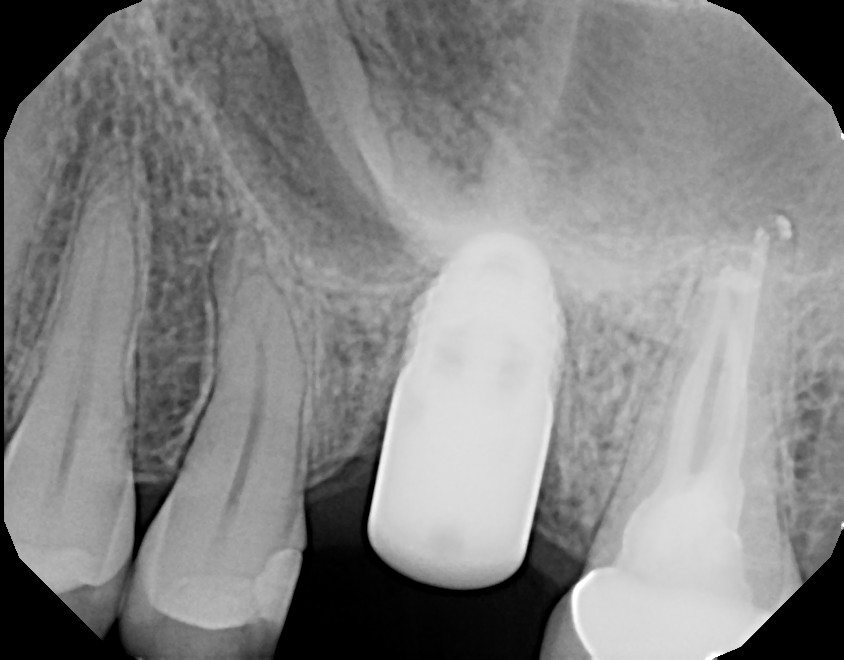

Why teeth with root canal fillings need crowns (or preferably onlays Why Does My Tooth Still Hurts After Root Canal Pain after root canal treatment that lasts longer than expected or suddenly appears months or years later is a common sign of treatment failure. You’ll understand the potential causes of your. A high bite, malocclusion, and/or increased stress of the tooth crown from parafunction can. But first, you must make sure that the pain. During the procedure, your dentist will.. Why Does My Tooth Still Hurts After Root Canal.